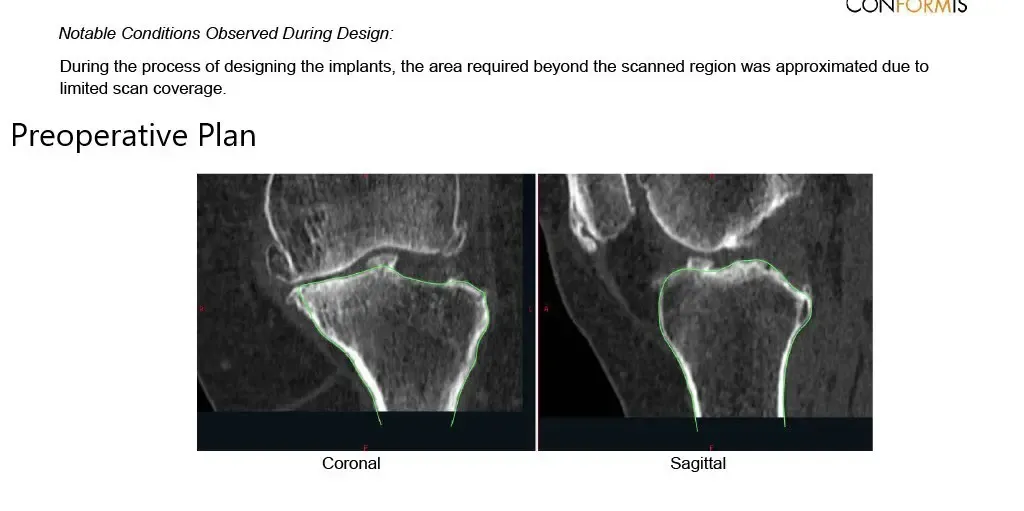

As a part of the preparation, a preoperative CT scan of the patient’s left knee along with ankle and hip was taken. The patient’s unique anatomy was utilized to build customized implants. Accurate bone cuts and offsets were determined from the CT scan data. Disposable bone jigs were made to match the patient’s unique anatomy. A preoperative plan was formed.

Complete Orthopedics patient specific surgical plan for a custom left knee replacement in a 71-year-old-male.

Complete Orthopedics patient specific surgical plan for a custom left knee replacement in a 71-year-old-male (scan-2)

Complete Orthopedics patient-specific surgical plan for a custom left knee replacement in a 71-year-old male (scan 3)